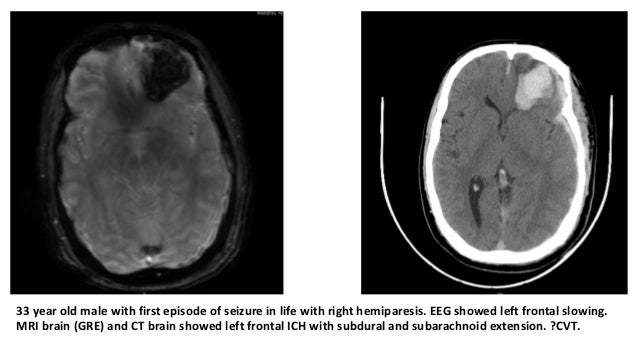

Diagnosis of epilepsy is dependent on history, physical and neurologic examination, labo-ratory testing as indicated, and electroen-cephalography and neuroimaging findings. The history should include events directly preceding the seizure, number of seizures in the past 24 hours, length and description of the seizure, focal aspects, and length of the postictal period. The need for laboratory testing is based on clinical context and may include blood glucose, blood counts, elec-trolyte panels (particularly sodium), lum-bar puncture in febrile patients, and urine toxicology (Figure 1). Electroencephalogra-phy should be used to confirm, but not to exclude, a diagnosis of epilepsy.12,13 Evalu-ation of a patient who has experienced a first seizure has previously been reviewed, including in American Family Physician.12-14